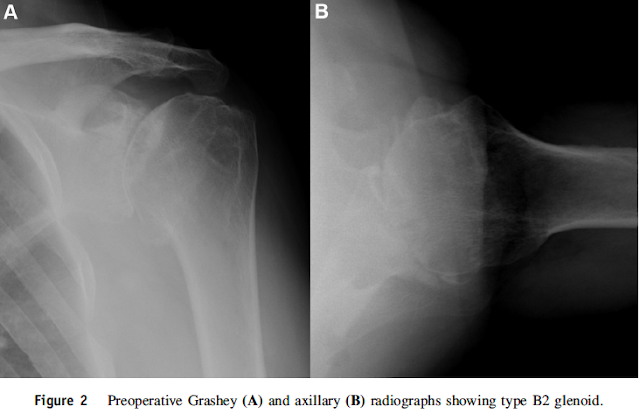

The article reports that both augmented and standard TSAs produced similar improvements in all ROM and PRO measures and that patients with augmented glenoid components were more likely to have type B2 or B3 deformities (P . .004).